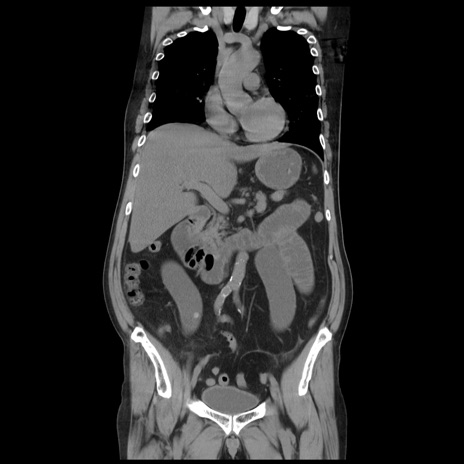

症例20(冠状断像)

【症例】 60歳代男性

【主訴】 腹部膨満、嘔吐

【現病歴】5日前頃より倦怠感を認め食事量減少し4日前の朝嘔吐、食事摂取困難となった。 3日前近医受診し点滴施行され整腸剤などを処方された。 当日他院を受診し、腹部膨満著明、炎症反応の上昇(CRP10.8、WBC11200)あり、紹介受診となる。

【身体所見】 意識JCS1 受け答えがはっきりしないBP 111/57mHg、 P 67bpm、、BT35.2°C、SpO2 97%(RA)、 腹部:膨隆、打診で鼓音あり、全体的に圧痛有り、腸蠕動音(-)、反跳痛ははっきりせず。

【データ】WBC 11400、CRP 14.20